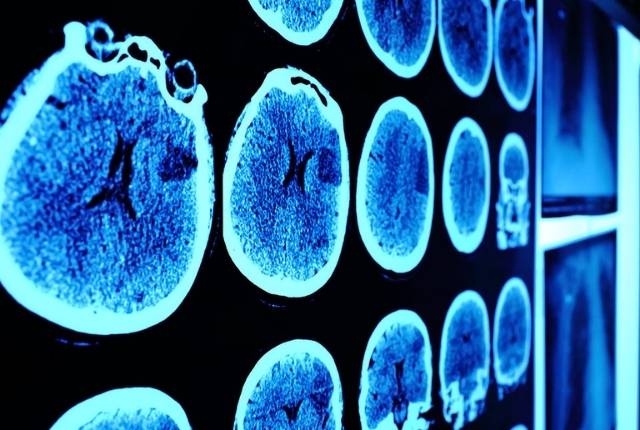

Comment diagnostiquer une tumeur au cerveau ?

Durant le rendez-vous, le médecin procédera à un examen clinique et à un interrogatoire, eux-mêmes associés par la suite à d'autres examens (scanner ou imagerie par résonance magnétique, dite IRM, par exemple), à des analyses sanguines, à l'analyse d'un échantillon de tissu tumoral (biopsie), voire à une ponction lombaire et à une consultation avec un neuro-oncologue.